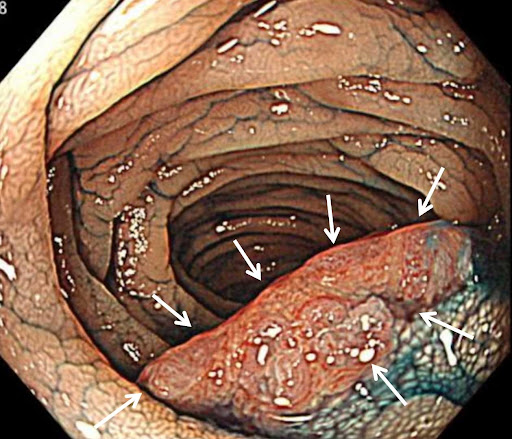

ESDは大きなポリープや薬剤でポリープが浮き上がらない場合に行われます。ESDは、電気メスを使用して切除する方法です。

最初に切除するポリープ周辺の粘膜にマーキングします。マーキング後、切除する部分の粘膜の下に生理食塩水やヒアルロン酸ナトリウムなどの薬剤を注入して、ポリープを浮き上がらせます。浮き上がった粘膜ごと病変と一緒に電気メスで剥離するように切除します。

EMRで対応できないような大きなポリープも切除できますが、EMRと比較すると熟練した医師の技術が必要で、治療時間がやや長くなる治療法です。基本的には入院治療となります。